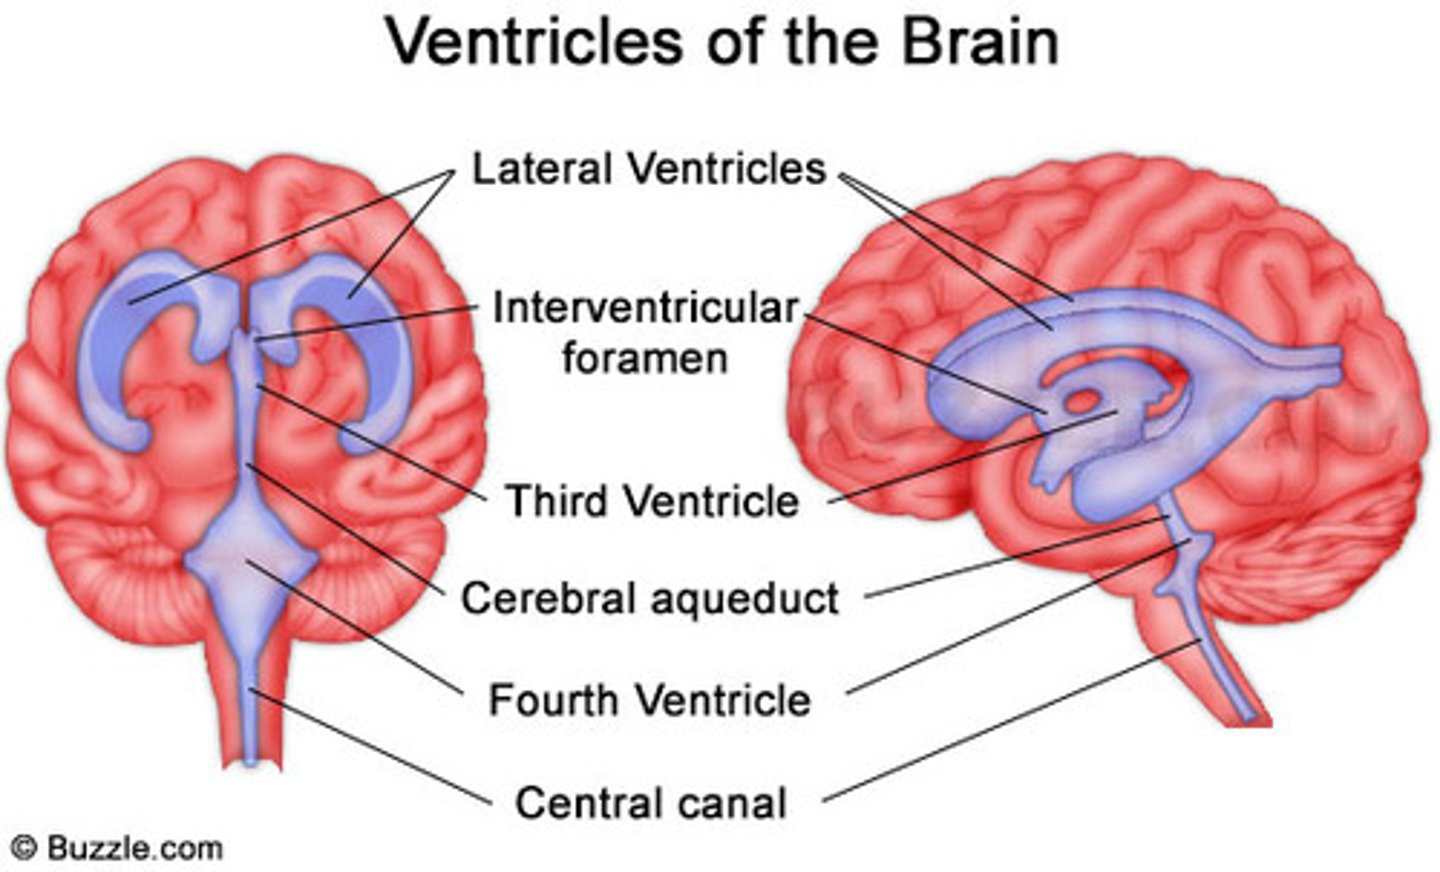

lateral ventricles

third ventricle

fourth ventricle

interventricular foramen

connects lateral ventricles to third ventricle

cerebral aqueduct

connects the third and fourth ventricles

choroid plexus

on the floor of all the ventricles, produces CSF

arachnoid villi

reabsorb/drain CSF into venous blood